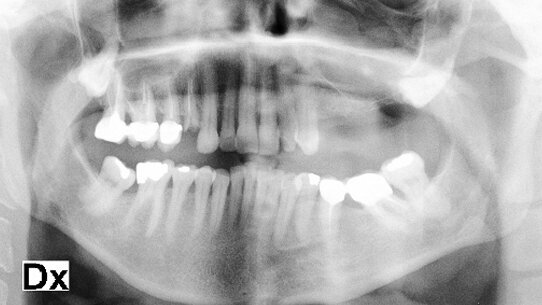

Come si evidenzia dalla Fig. 1 il paziente di sesso femminile (49 anni di età) in buone condizioni di salute generale, necessitava di una procedura di grande rialzo del seno mascellare per posizionamento di impianti nel settore diatorico sinistro. È stato utilizzato per questo caso un apparecchio di centrifuga del sangue (Medifuge, Silfradent, S. Sofia, Italia) che ha permesso di ottenere il concentrato ricco di fattori di crescita (Figg. 2, 3). La letteratura ha evidenziato come questo strumento differentemente da altri consente l’ottenimento di un CGF con una concentrazione di fattori di crescita nel buffy coat che supera del 300% i risultati ottenuti fino a oggi dalle sistematiche più evolute presenti sul mercato (Rondella et al 2010). Inoltre usando l’apparecchio Medifuge, è possibile usare tutte le fasi della separazione ematica, parti rosse comprese, che rappresenta un’innovazione rispetto alle metodiche tradizionali. L’altra caratteristica importante del nostro intervento è stato il fatto che il concentrato è stato miscelato con il biomateriale all’interno della specifica centrifuga (Silfradent, S. Sofia, Italia) in modo da ottenere un composto ben amalgamato in cui i fattori di crescita fossero equamente distribuiti con il biomateriale (Fig. 4). Ciò ha consentito di procedere al rialzo di seno ottenendo quindi risultati ottimali (Figg. 5, 6).